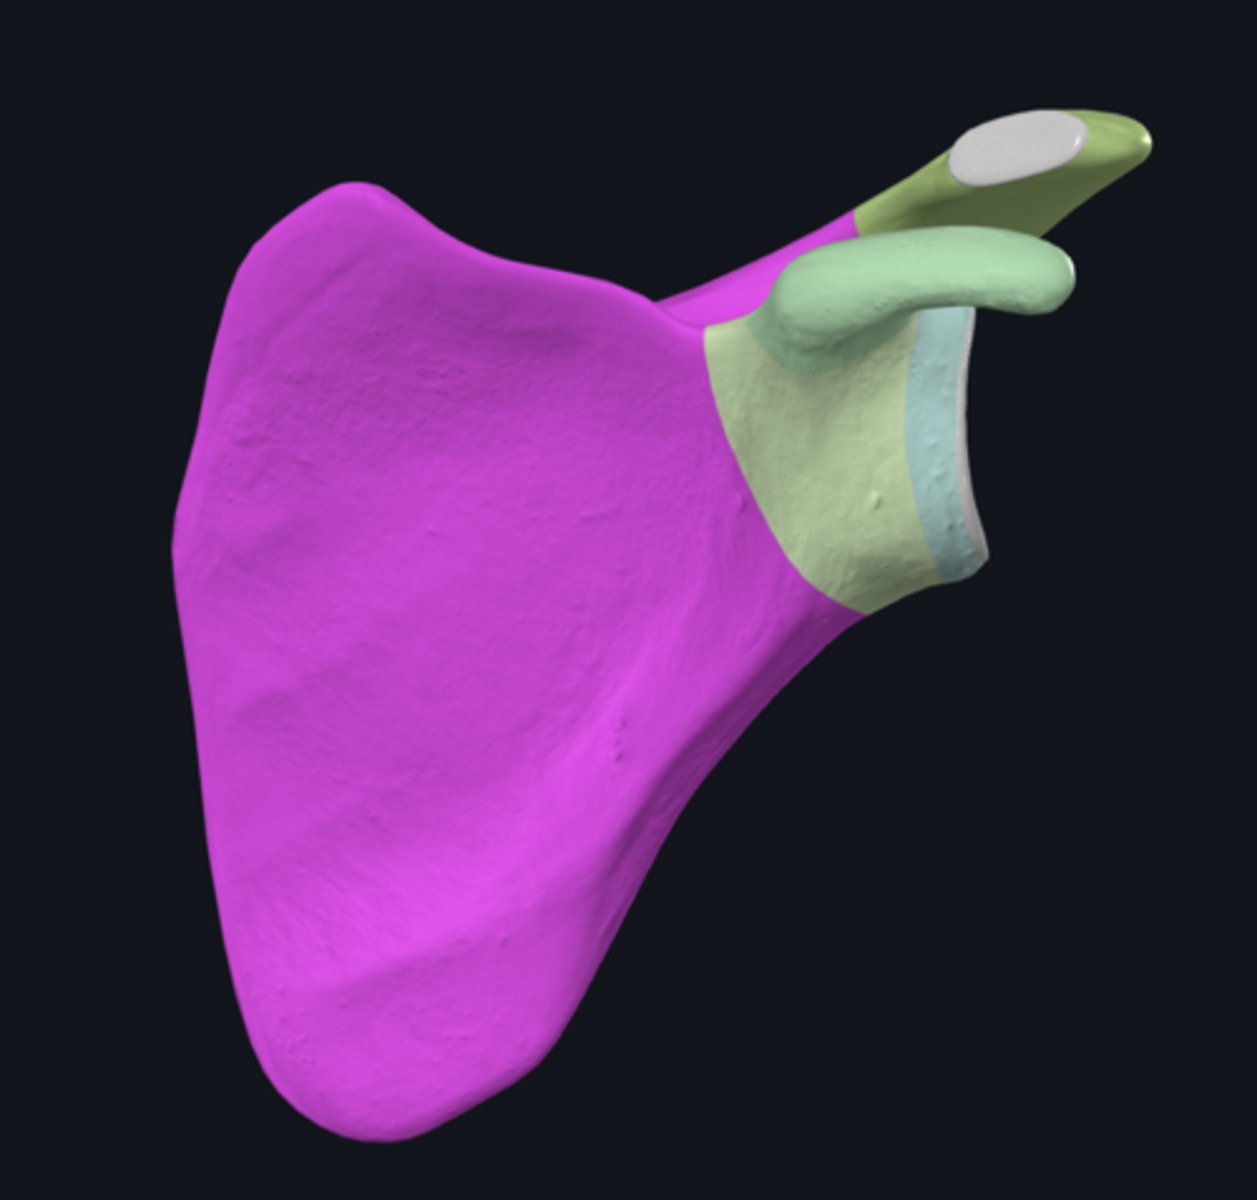

Acromion

Superior angle of scapula

Coracoid process

lateral border of scapula

medial border of scapula

inferior angle of scapula

body of scapula

Head of scapula

neck of scapula

costal surface of scapula

lateral angle of scapula

posterior surface of scapula

scapular notch

superior border of scapula

acromial angle

clavicular facet

glenoid fossa

infraglenoid tubercle

infraspinous fossa

spine of scapula

supraglenoid notch

subscapular fossa

supraglenoid tubercle

supraspinous fossa